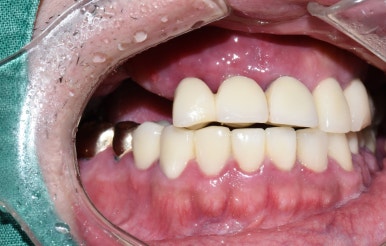

어금니 임플란트 완성 및 임플란트 치료중 사진 (왼) / 완성 후 사진(오른쪽)

어금니 임플란트가 완성된 모습(왼쪽) 및 앞니 임플란트 진행중인 사진과

완성된 사진

기존의 다른 치아와 다른 임플란트, 보철물과 조화를 이루는 앞니 임플란트

완성된 입안에서의 모습 사진입니다.

화살표 표시한 부분내의 치아가 이번에 진행한 임플란트입니다.